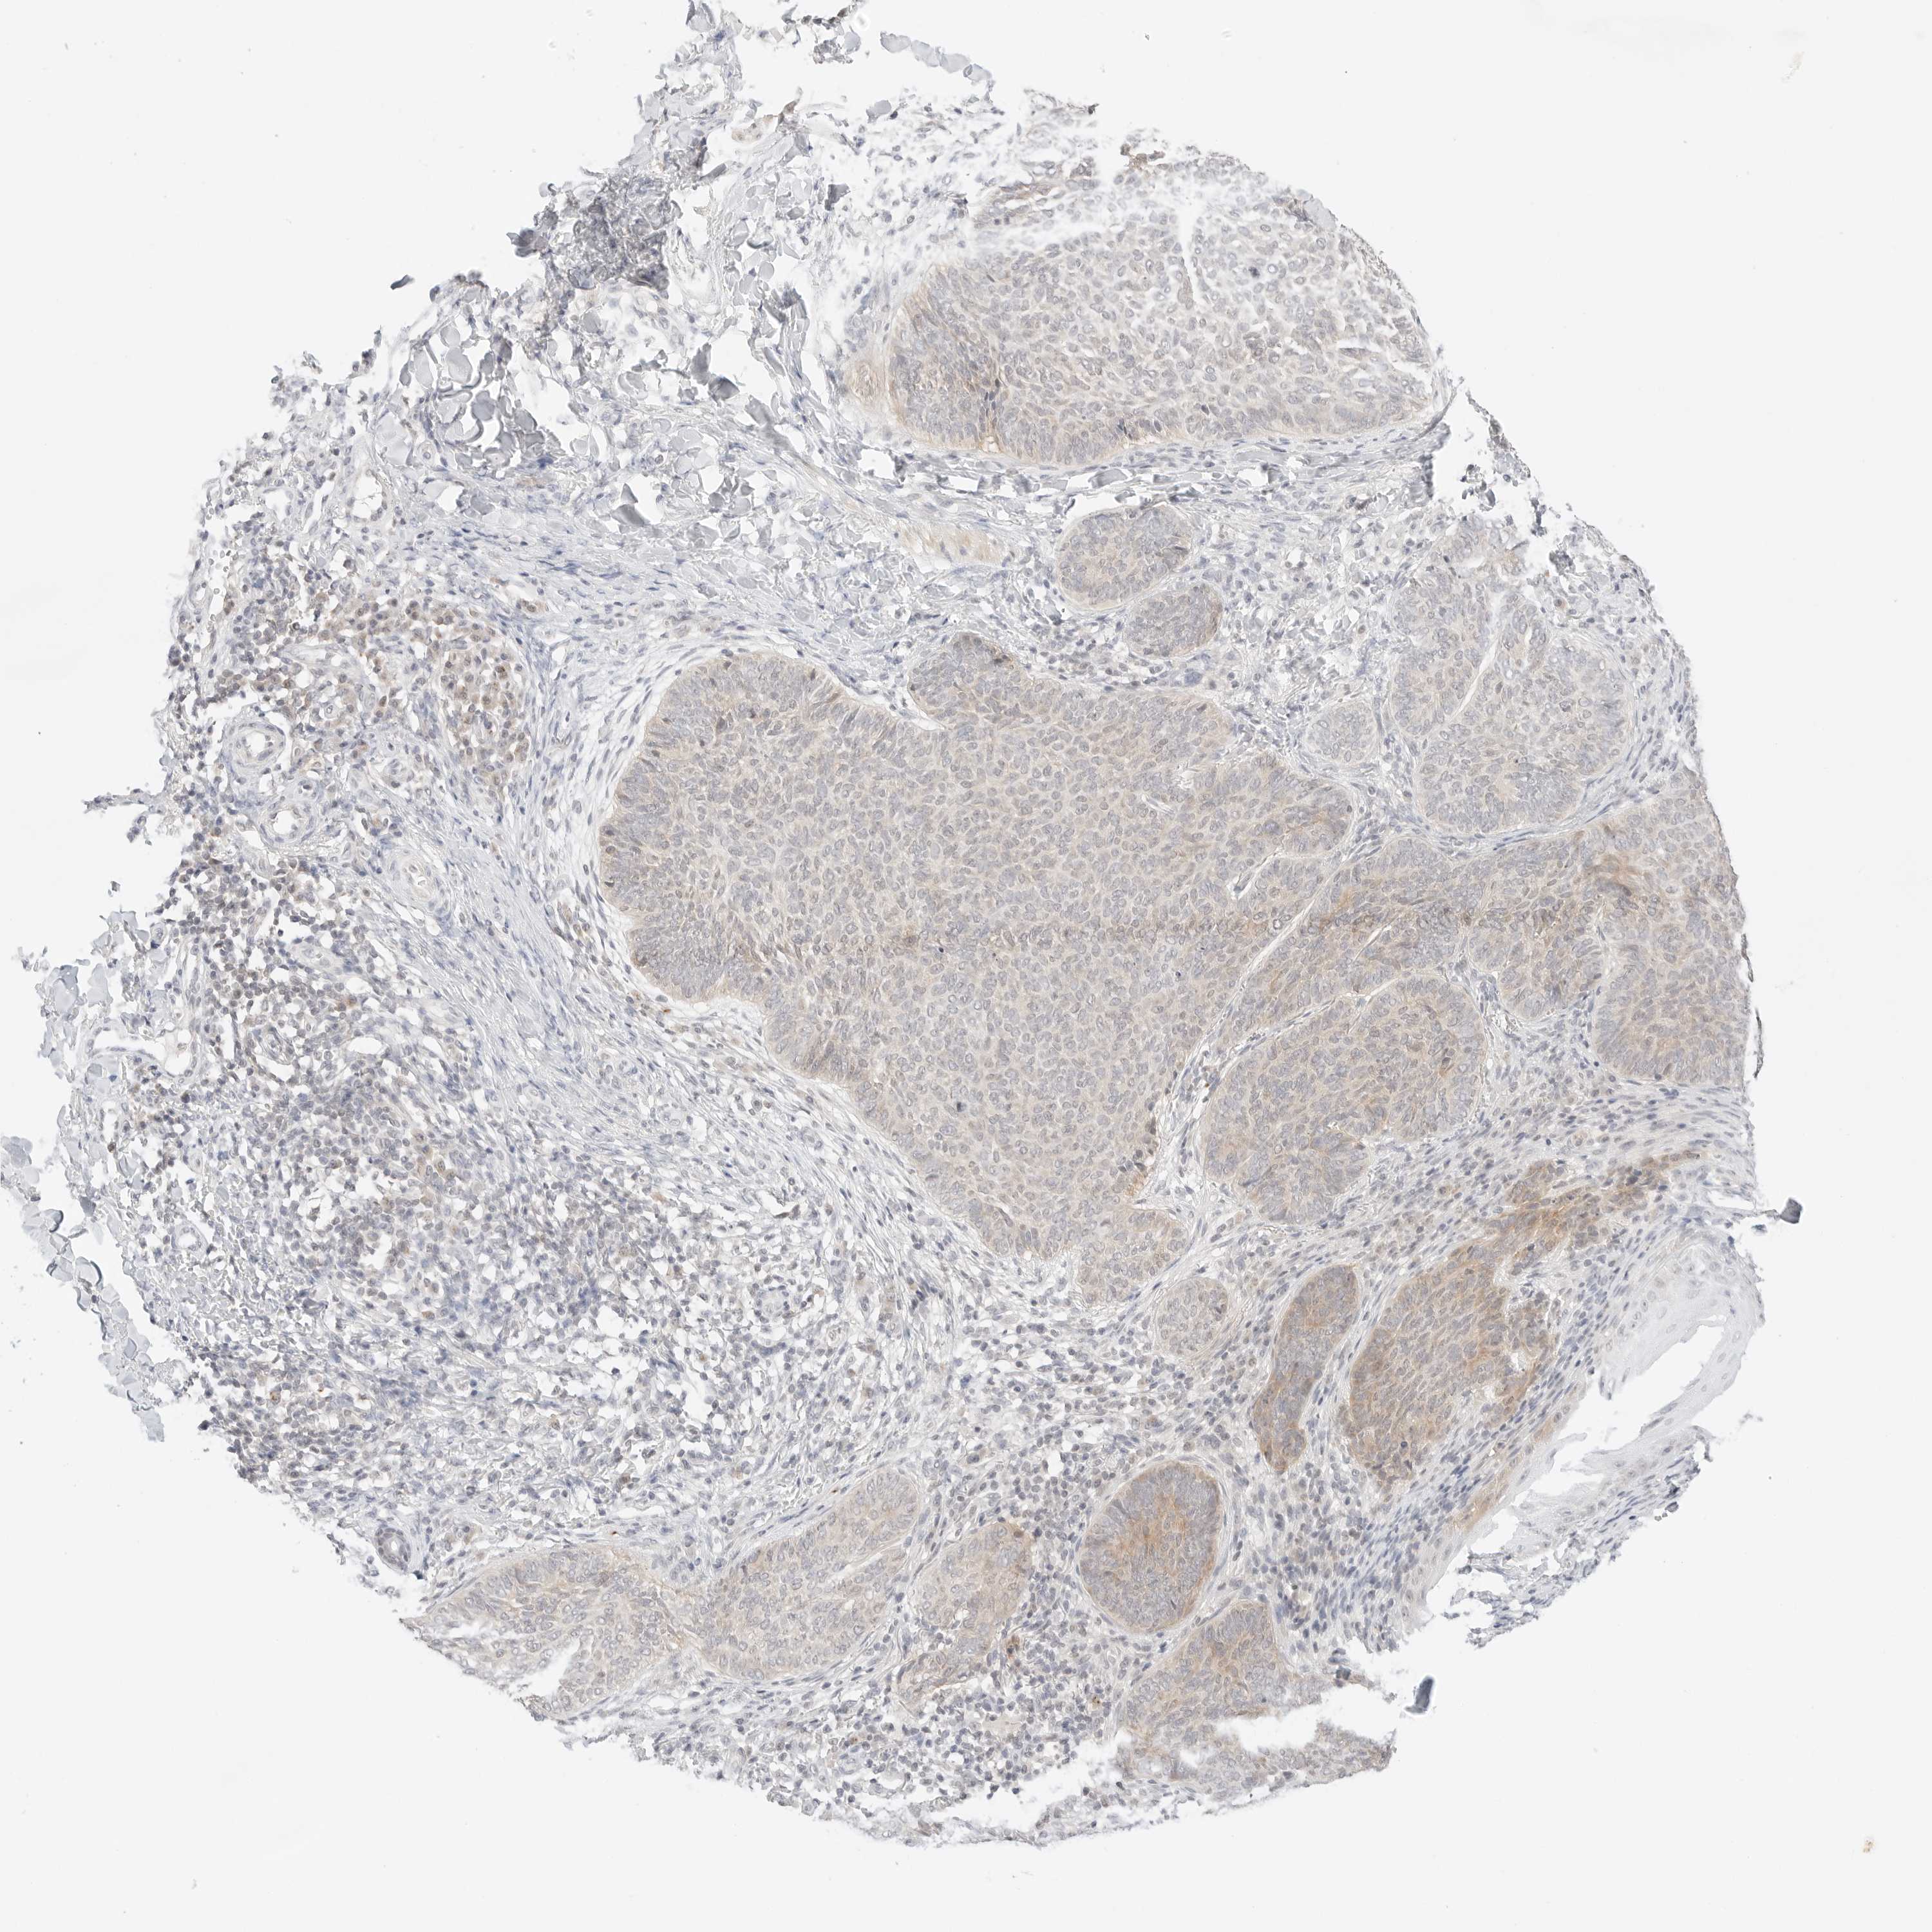

SKIN CANCER - Protein expressioni

A mouse-over function shows sample information and annotation data. Click on an image to view it in a full screen mode. Samples can be filtered based on level of antibody staining by selecting one or several of the following categories: high, medium, low and not detected. The assay and annotation is described here.

Each image is clickable and will lead to virtual microscopy that enables deeper exploration of all samples and also displays staining intensity scores, fraction scores and subcellular localization as well as patient and tissue information for each sample.

Antibody HPA018122

Basal cell carcinoma